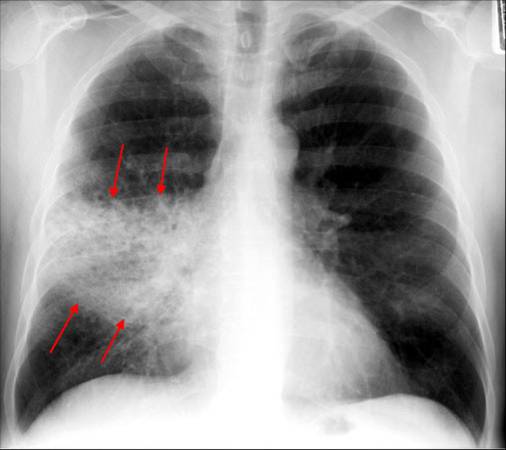

weekly clinical round for undergraduate from 8 to 11 AM during which interpretation of CHEST X rays was done for all cases of cardiothoracic surgery, gived by 2 staf member for 3 months